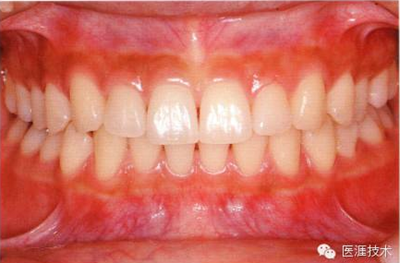

健康且正常的牙周組織臨床圖像

50歲女性的健康口腔內(nèi)部

圖為50歲女性,無特殊全身疾病,不抽煙。持續(xù)保養(yǎng)6年。無填充物等問題,依照患者本人要求持續(xù)觀察。牙周組織臉頰側(cè)雖見部分萎縮,但X線牙片顯示牙間無骨吸收現(xiàn)象,保持著比較健康的狀態(tài)。